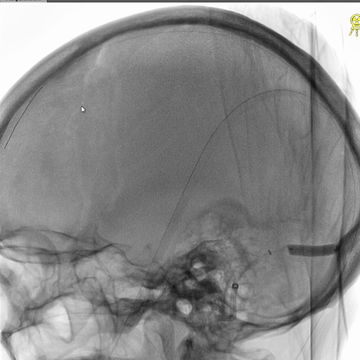

直窦再次微导管造影:直窦血液引流可。

6*30mm球囊扩张右侧横窦-乙状窦和颅底位置颈内静脉,辅以球囊滑动技术。

介入治疗后右侧颈动脉造影:上矢状窦、直窦和右侧横窦-乙状窦均见显影,右侧横窦局部狭窄明显。